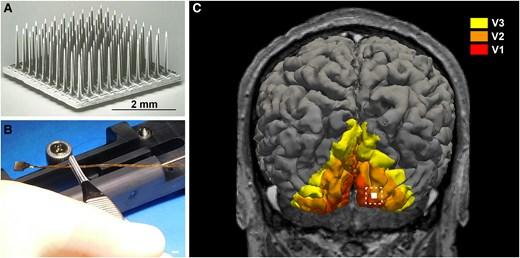

连接计算机与大脑的,是一个由100个微电极组成的阵列,边长4毫米。医生通过一次小型开颅手术,把阵列植入参与者的初级视觉皮层,也就是负责处理视觉信息的大脑区域。

A 犹他电极阵列及比例尺;B 研究人员手持的犹他电极阵列;C 植入部位示意图 | 参考文献[1]